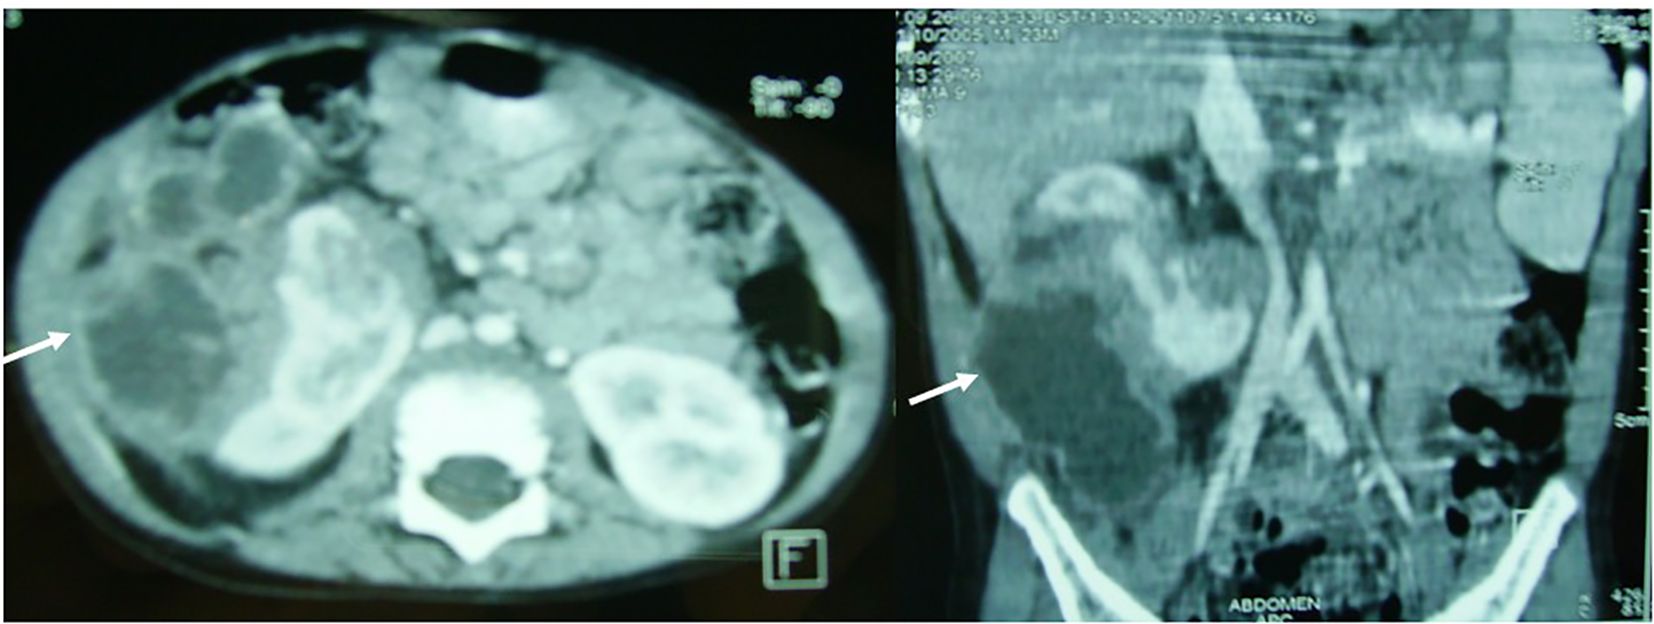

Background: Focal xanthogranulomatous pyelonephritis (XGP) is a rare chronic renal inflammatory disorder in children that often mimics renal neoplasms, complicating diagnosis and management. Methods: We describe two pediatric cases of focal XGP managed at our institution and provide a descriptive review of the literature (1975–2024), analyzing clinical presentation, imaging features, management strategies, and outcomes of this disease. Results: Case 1: A 2-year-old boy presented with a febrile right flank mass and systemic inflammation. CT Scan revealed an 80 mm multilocular renal mass. Surgical drainage and biopsy confirmed focal XGP, and targeted antibiotics led to complete resolution with preserved renal function at two-year follow-up. Case 2: A 10-year-old girl presented with a 40 mm left renal mass and systemic inflammatory signs. CT-guided aspiration and histopathology confirmed focal XGP. She was managed conservatively with intravenous and oral antibiotics, achieving complete resolution and normal renal function at seven-year follow-up. Literature review of 34 pediatric XGP cases (median age 11.1 years) showed that 53% were focal lesions. Conservative management with antibiotics, with or without drainage, succeeded in 64% of cases, and overall outcomes were favorable, with stable renal function and no reported mortality. Conclusion: This combined case series and descriptive literature review highlights that conservative, kidney-sparing management is a feasible and effective approach in selected pediatric focal XGP cases. Multicenter collaborations are needed to define standardized diagnostic and therapeutic protocols.